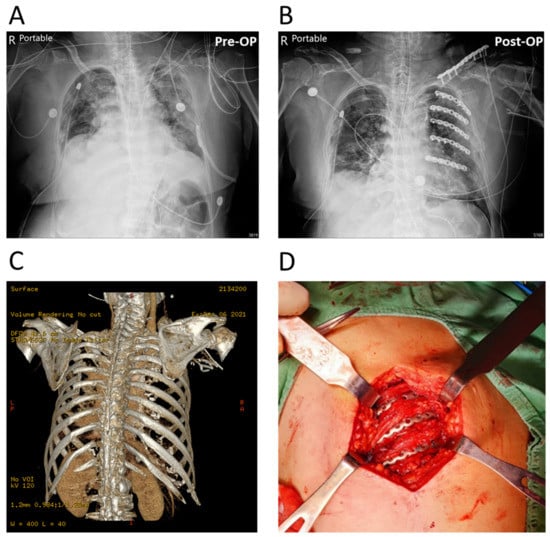

The configurations of the APS Rib Fixation System and Mini bone plate are illustrated in Figure 1 and Figure 2, respectively. Notably, the “pre-contoured” structure of the APS plate (R = 166 mm) facilitated an optimized fit to the average rib shape, which minimized intraoperative bending (Figure 1). Meanwhile, the traditional Mini bone plate required manual bending prior to implantation (Figure 2). A representative case of the rib-repairing technique using the APS plates is shown in Figure 3.

Figure 3. A representative case of multiple rib fractures repaired with APS plates. (A,B) AP radiograph of pre-operation (Pre-OP) and post-operation (Post-OP). (C) Three-dimensional CT reconstruction image of the injury. (D) Intraoperative photograph showing the rib-repairing technique with implanted APS plates.